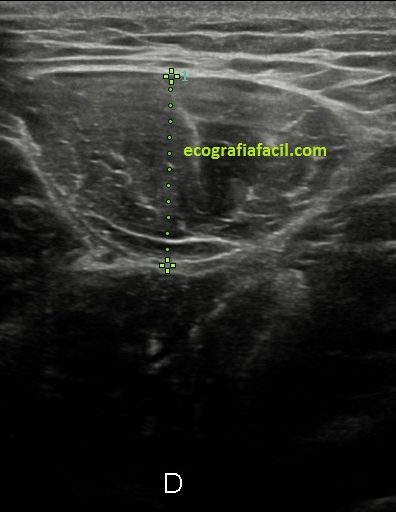

Acto seguido procedo a las mediciones en ambos planos:

Compruebo los hallazgos en ambos planos. (Fig 4).

Observa en el corte transverso de la misma región un Recto Anterior sano, ecográficamente perfecto, el de la figura 5,y compara con la imagen inmediatamente superior, figura 4, donde vemos el músculo retraído cambiado en su ecoestructura, edematoso en su contorno, con un aspecto claramente patológico.